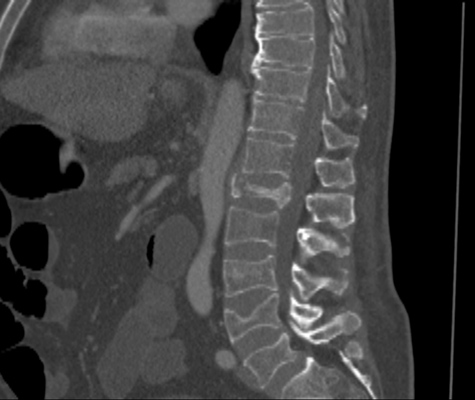

We trained and evaluated the method with five sets of CT and MR scans that visualize the spine. Reference segmentation masks for four of these datasets are publicly available, which allowed for a comparison with other publications that used the same data. Examples of images from the datasets are shown in Figure 3.

The thoracolumbar spine CT dataset consists of 15 dedicated spine CT scans that visualize all thoracic and lumbar vertebrae. It was originally used for the spine segmentation challenge held in conjunction with the Computational Spine Imaging (CSI) workshop at MICCAI 2014 (Yao et al., 2016). All subjects were young adults ( years) without vertebral fractures who were scanned with IV-contrast administration. The scans were reconstructed to in-plane resolutions of and slice thicknesses of . Semi-automatically obtained reference segmentations were provided by the challenge organizers. To allow for a comparison with the challenge results, we used the same data split with 5 scans for evaluation and the remaining 10 scans for training and development.

The xVertSeg.v1 dataset consists of 15 lumbar spine CT scans of subjects with compression fractures of various grades and types (Ibragimov et al., 2017). Manual reference segmentations are available for the lumbar vertebrae and were defined through a consensus reading of two observers. The scans were reconstructed to in-plane resolutions of and slice thicknesses of . There are currently two other publications that used the same dataset, but with different evaluation/training separation (Janssens et al., 2018; Sekuboyina et al., 2017). We therefore used the scans for evaluation and the remaining 10 scans for training.

The low-dose chest CT dataset consists of 55 scans from the National Lung Screening Trial (The National Lung Screening Trial Research Team, 2011). These scans were acquired for lung imaging and visualize in addition to the lungs a variable section of the thoracic and upper lumbar vertebrae. The scanned subjects were heavy smokers aged 50 to 74 years and therefore at increased risk for vertebral compression fractures due to their advanced age and smoking history. The scans were acquired with low radiation dose and reconstructed to in-plane resolutions of and slice thicknesses of . We created manual and semi-automatic reference segmentations for this dataset: 10 scans were used for evaluation and were therefore fully manually annotated by drawing along the contour of each vertebra in sagittal slices using an interactive live wire tool (Barrett and Mortensen, 1997). The contours were converted into segmentation masks, in which inaccuracies and other mistakes were corrected voxel-by-voxel. An additional set of 5 scans was annotated in the same way and was used to train a preliminary version of the network. This network was used to predict rough segmentations in the remaining 40 scans. These rough segmentations were manually inspected and corrected voxel-by-voxel, and were used for training of the final network. This strategy enabled us to create a large training set with substantially less manual annotation effort compared to fully manual segmentation, which is not necessarily needed for training data. Additionally, a second observer fully manually annotated two scans from the evaluation set for an estimation of the interobserver agreement. All fully manual and semi-automatic segmentations were performed in sagittal views by observers who received detailed instructions beforehand. Additionally, all segmentations were validated by an experienced radiologist.

The lumbar spine CT dataset consists of 10 scans of healthy subjects and corresponding manual reference segmentations of the lumbar vertebrae (Ibragimov et al., 2014; Korez et al., 2015). The scans were reconstructed to in-plane resolutions of and slice thicknesses of . Because this dataset is the smallest of the datasets that we included, it was used for an external evaluation of our supervised approach. Scans from this dataset were therefore only used for evaluation and were not part of the training set.

The lumbar spine MR dataset consists of 23 T2-weighted turbo spine echo MR images acquired at 1.5T in sagittal orientation (Chu et al., 2015). The scans have a resolution of . Manual reference segmentations are available for 7 vertebrae (T11-L5) in all scans. These reference segmentations contain only the vertebral bodies, not the entire vertebrae.